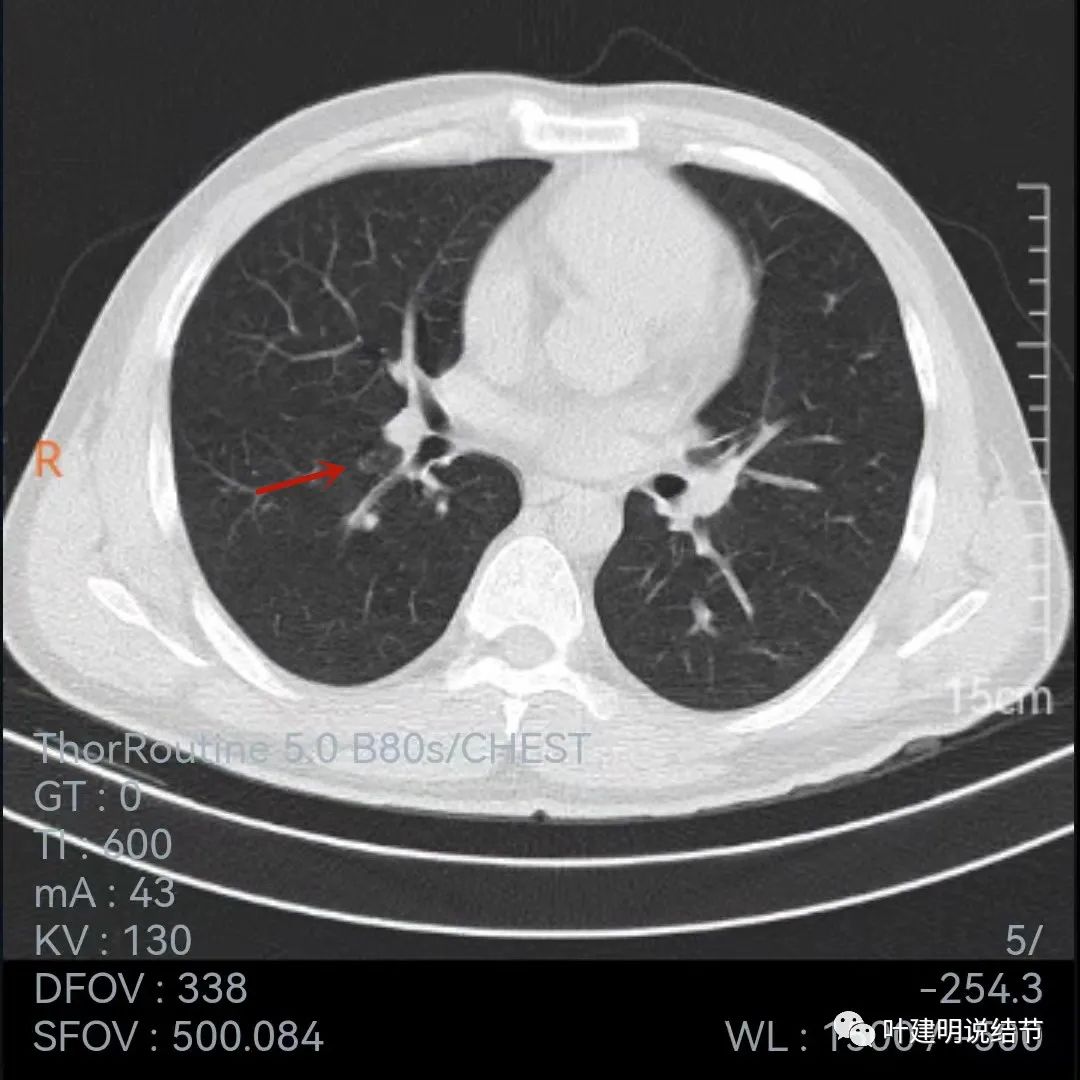

我们再来看2019年的片子:

上面是2019年5月份的片子,不是薄层,只有这两个层面见到病灶,是实性小结节,叶间裂似略有牵拉,病灶边缘比较光滑,密度相对较均匀,没有毛刺或血管征,单看应该良性结节可能性大,至少先随访。